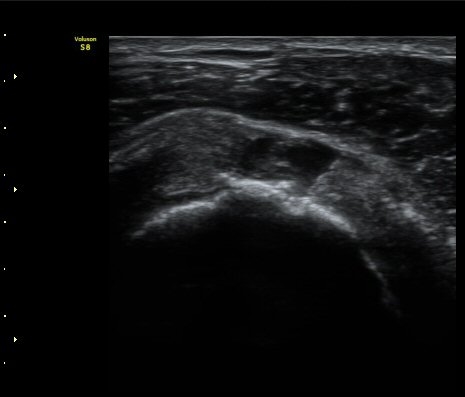

ÃÊÀ½ÆÄ °Ë»ç

À̵ιڱ٠Á¾´Ü¸é°Ë»ç»ó ƯÀÌ ¼Ò°ßÀ» º¸ÀÌÁö ¾ÊÀ¸³ª(±×¸² 1)  ŽÃËÀÚ¸¦ ¾Æ·¡·Î À̵¿ÇÏ´Ï

°ß°©ÇÏ±Ù°Ç ³»Ãø¿¡¼­ ¼ö¾×Àú·ù°¡ °üÂûµÈ´Ù(±×¸² 2).